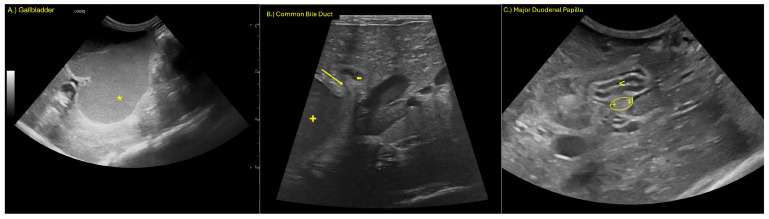

Ultrasonographic evaluation revealed marked dilation of the gallbladder and CBD (Figure 1). Both contained a marked amount of gravity-dependent echoic material with hyperechoic foci and speckles, alongside non-gravity-dependent anechoic material. The walls of the gallbladder and CBD were moderately thickened and hyperechoic, and they exhibited mild irregularity.

The CBD demonstrated abrupt luminal tapering proximal to the major duodenal papilla (Figure 1B), while the papilla itself appeared within normal limits sonographically. Moderate dilation of the intrahepatic bile ducts was noted. The pancreatic duct was mildly dilated at its most distal aspect (Figure 1B). The stomach was moderately displaced toward the right cranial abdomen, consistent with mass effect from the adjacent biliary structures. A mild amount of anechoic peritoneal effusion was identified.

The findings were consistent with an extrahepatic biliary obstruction, most likely at or just proximal to the major duodenal papilla, secondary to a mucous plug, stricture, or other causes of obstruction. Reactive peritoneal effusion and mild pancreatic ductal dilation may reflect early secondary inflammatory or pressure-related changes.